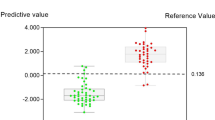

The diagnostic prediction model based on all these predictors demonstrated good accuracy in predicting benign and malignant conditions. The accuracy for predicting benign lymphadenopathy was 92.2% (AUROC = 0.92; 95% CI 0.87, 0.96) with a sensitivity of 88% and specificity of 78% (Fig. 2), while for predicting malignant lymphadenopathy, it was 98.6% (AUROC = 0.98; 95% CI 0.94, 0.99) with a sensitivity of 91% and a specificity of 85% (Fig. 3).

Upon evaluating the ability of the model to differentiate between abnormal benign lymphadenopathy and malignant cases from reactive hyperplasia, it was found to have superior discriminatory power for malignancy (AUROC = 98.6%) compared to abnormal benign lymphadenopathy (AUROC = 92.2%). Nonetheless, the model maintained a high accuracy in predicting both conditions. Moreover, when considering the model’s findings, unnecessary lymph node biopsies could be reduced by nearly 45% in the reactive hyperplasia group, potentially mitigating the severity of surgical complications, anesthesia administration, treatment costs, and school or work absenteeism for patients.

The model demonstrated high accuracy for predicting benign (92.2%) and malignant (98.6%) conditions. However, using the same dataset for both development and validation could overestimate the model’s performance. The ROC curves and AUC values for both benign and malignant lymphadenopathy predictions highlight the model’s strong diagnostic capabilities. Despite this, the sensitivity and specificity values reveal that while the model is highly effective in identifying true-positive cases, there are still instances of false positives and false negatives. The high specificity for malignant predictions (85%) ensures the model’s reliability for identifying malignancies, but the sensitivity and specificity for benign predictions (88% and 78%, respectively) suggest that some benign cases may still be misclassified.